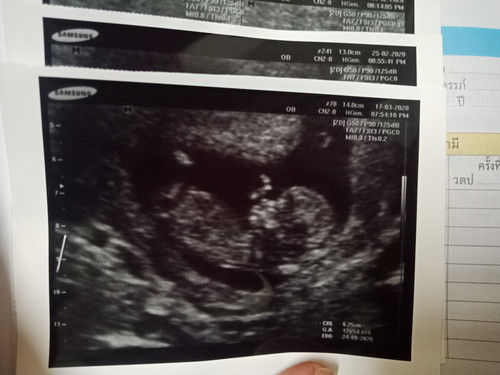

12 wk+1 d กับพาหะธาลัสซีเมียในแม่

แม่ๆคนไหนเป็นพาหะธาลัสซีเมียบ้างคะ บ้านนี้ไม่เคยรู้ว่าครอบครัวมีภาวะธาลัสซีเมียมาก่อน จนมาถึงวันนี้ แม่เป็นพาหะ type e ต้องรอลุ้นเลือดพ่ออีกทีสิ้นเดือน ควรวิตกไหมน้อออ ??? ใจนึงก็กลัว ใจนึงก็มั่นใจว่าไม่น่ามีอะไรร้ายแรงจากที่คุยกับคุณหมอ เอาเป็นว่าอวดเด็กน้อยก่อนน้าาาาา